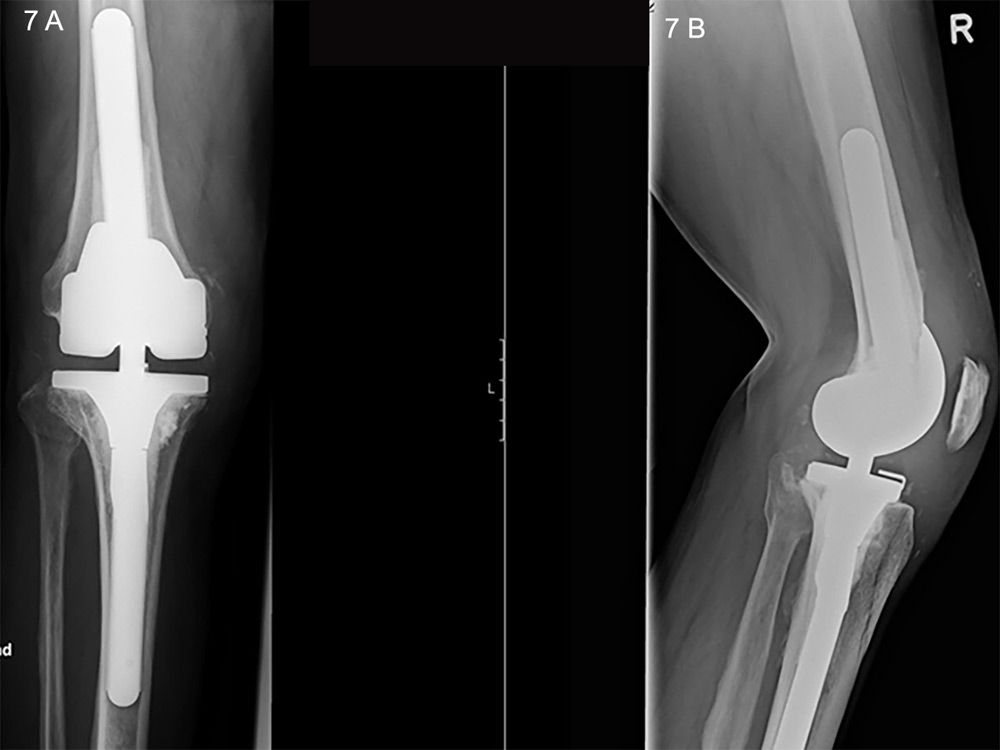

Figure 7

A. Anteroposterior X-ray of an hinged revision prosthesis. B. Lateral view in the same joint.

Periprosthetic infections are a devastating problem and account for 20% of all primary knee revisions (fig. 6) [84]. They can be classified as early (<3 months after surgery), delayed (3–24 months after surgery) or late “chronic” (>24 months after surgery). Early and delayed infections are typically acquired during surgical implantation, whereas late infections are the result of haematogenous seeding [96]. There is controversy over the classical definition of a chronic infection being related to the passage of time, as the pathological mechanism is dependent on the formation of a biofilm. A reliable, increasingly used parameter is the interval from symptom onset, where a 3-week cut-off has been used to define a chronic infection [97]. It is important to note that only an open tissue biopsy is sufficient for confirmation of diagnosis, the sensitivity of which by far overweighs that of joint fluid aspiration [96]. Once the diagnosis of an infection is made, a radical surgical intervention that takes into account the nature of the infection and the microorganism involved has to be planned; antibiotic treatment is an adjunct but does not have solitary role. The intervention could take the form either of a radical debridement and exchange of the polyethylene inlay in the case of acute infection, or a single-stage procedure, in which the implant is removed and replaced by a second after radical debridement, or a two-stage procedure, with implantation of an antibiotic-augmented cement spacer to establish aseptic conditions before final revision, the latter of which is the gold-standard for chronic infections [98, 99]. Figure 7 shows an implanted revision prosthesis.